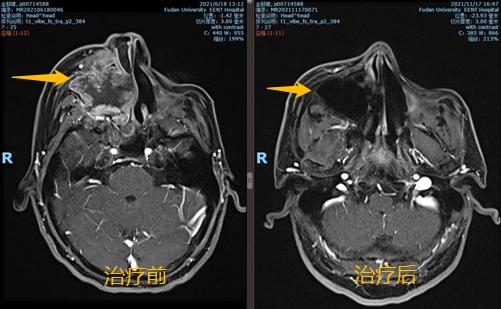

将病情和治疗新进展与患者及家属充分沟通后,医生和患者及家属达成了一致的想法,愿意先采用化疗联合免疫治疗的方法一试,其间密切跟踪右侧上颌窦肿瘤退缩情况。患者的充分信任和医生的努力换来了可喜的结果:一个疗程治疗后,患者的右半边头痛即得到了缓解,面部肿胀开始消退。两个疗程后行鼻腔鼻窦磁共振检查,肿瘤完全退缩。

继续乘胜追击!目前患者已完成6疗程的化疗和9疗程的PD-1抑制剂免疫治疗,正在继续免疫治疗维持中,患者鼻塞、牙痛、头痛等症状已完全缓解,生活基本正常。最新的磁共振显示,局部肿瘤已被完全控制!划重点!